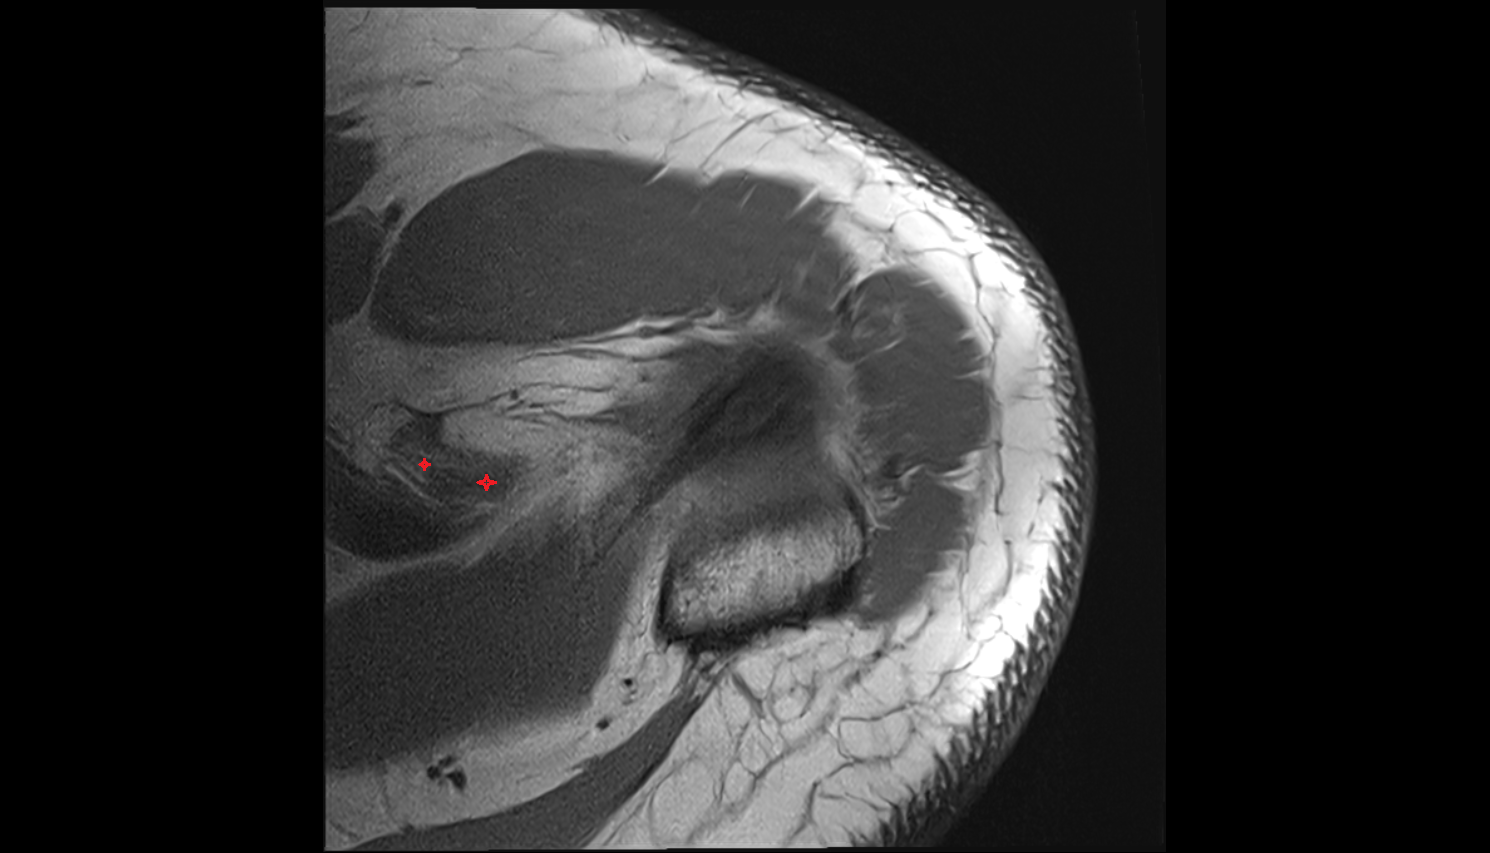

- Shoulder joint (glenohumeral joint)

- Glenoid labrum

- Glenohumeral joint capsule